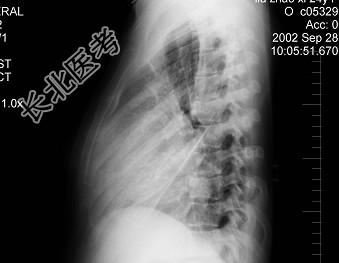

- 单项选择题女,24岁, 干咳1个月出现胸闷气急,活动时明显, 查体颈静脉显露,胸片如图, 最可能的诊断为 ( )

B、心包积液